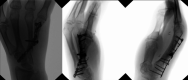

Multifocal chondrosarcoma of the hand: Case report and review of the literature

Few multifocal hand chondrosarcomas have been reported. To our knowledge, this report is the first to describe multifocal hand chondrosarcoma in a patient with no evidence of prior enchondroma, Ollier's disease, or Maffucci syndrome.